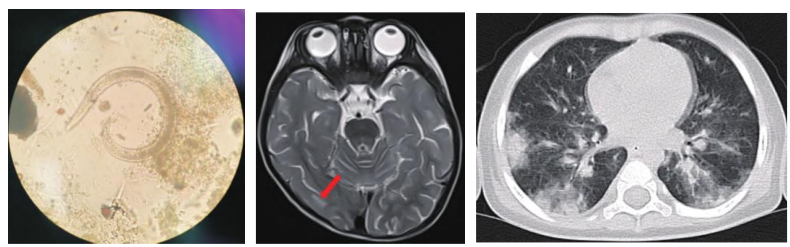

“这种巴掌大的蜗牛其实并非广东‘本地蜗牛’,它们的学名是褐云玛瑙螺,通常被称为‘非洲大蜗牛’。”华南农业大学资环学院昆虫学系何晓芳副教授介绍,非洲大蜗牛能够对500多种植物产生危害,包括农作物、林木、果树、蔬菜、花卉等,是许多人畜寄生虫和病原菌的中间宿主,尤其会传播结核病和嗜酸性脑膜炎,已被列入《中国第一批外来入侵物种名单》。

非洲大蜗牛体态魁梧,是我们常见的本土蜗牛的数倍之大。与本土蜗牛相比,非洲大蜗牛的体内携带了更多的人类病原菌和耐药病原菌。这不仅增加了人类感染的可能性,同时还使得治疗变得更为困难。

“蜗牛(螺)都是可食用的,但是非洲大蜗牛以及很多蜗牛(螺)是广州管圆线虫的中间宿主,为了解馋而冒健康风险,得不偿失!”何晓芳介绍,近年在广州及珠三角的一些蜗牛(螺)调查中,广州管圆线虫的感染率在2%-47.06%之间。广州地区也有儿童广州管圆线虫病收治的报道。其中某些病例有食生田螺、进食蜗牛、接触福寿螺、接触蛞蝓的流行病学史。如果误食可能会患上广州圆管线虫嗜酸性脑膜炎等疾病,可能危及生命!

非洲大蜗牛的危害还不止于此。它爬行时留下的黏液中可能也携带着病原体,如果它爬行过水果、蔬菜等,也有可能会间接传染给人类。